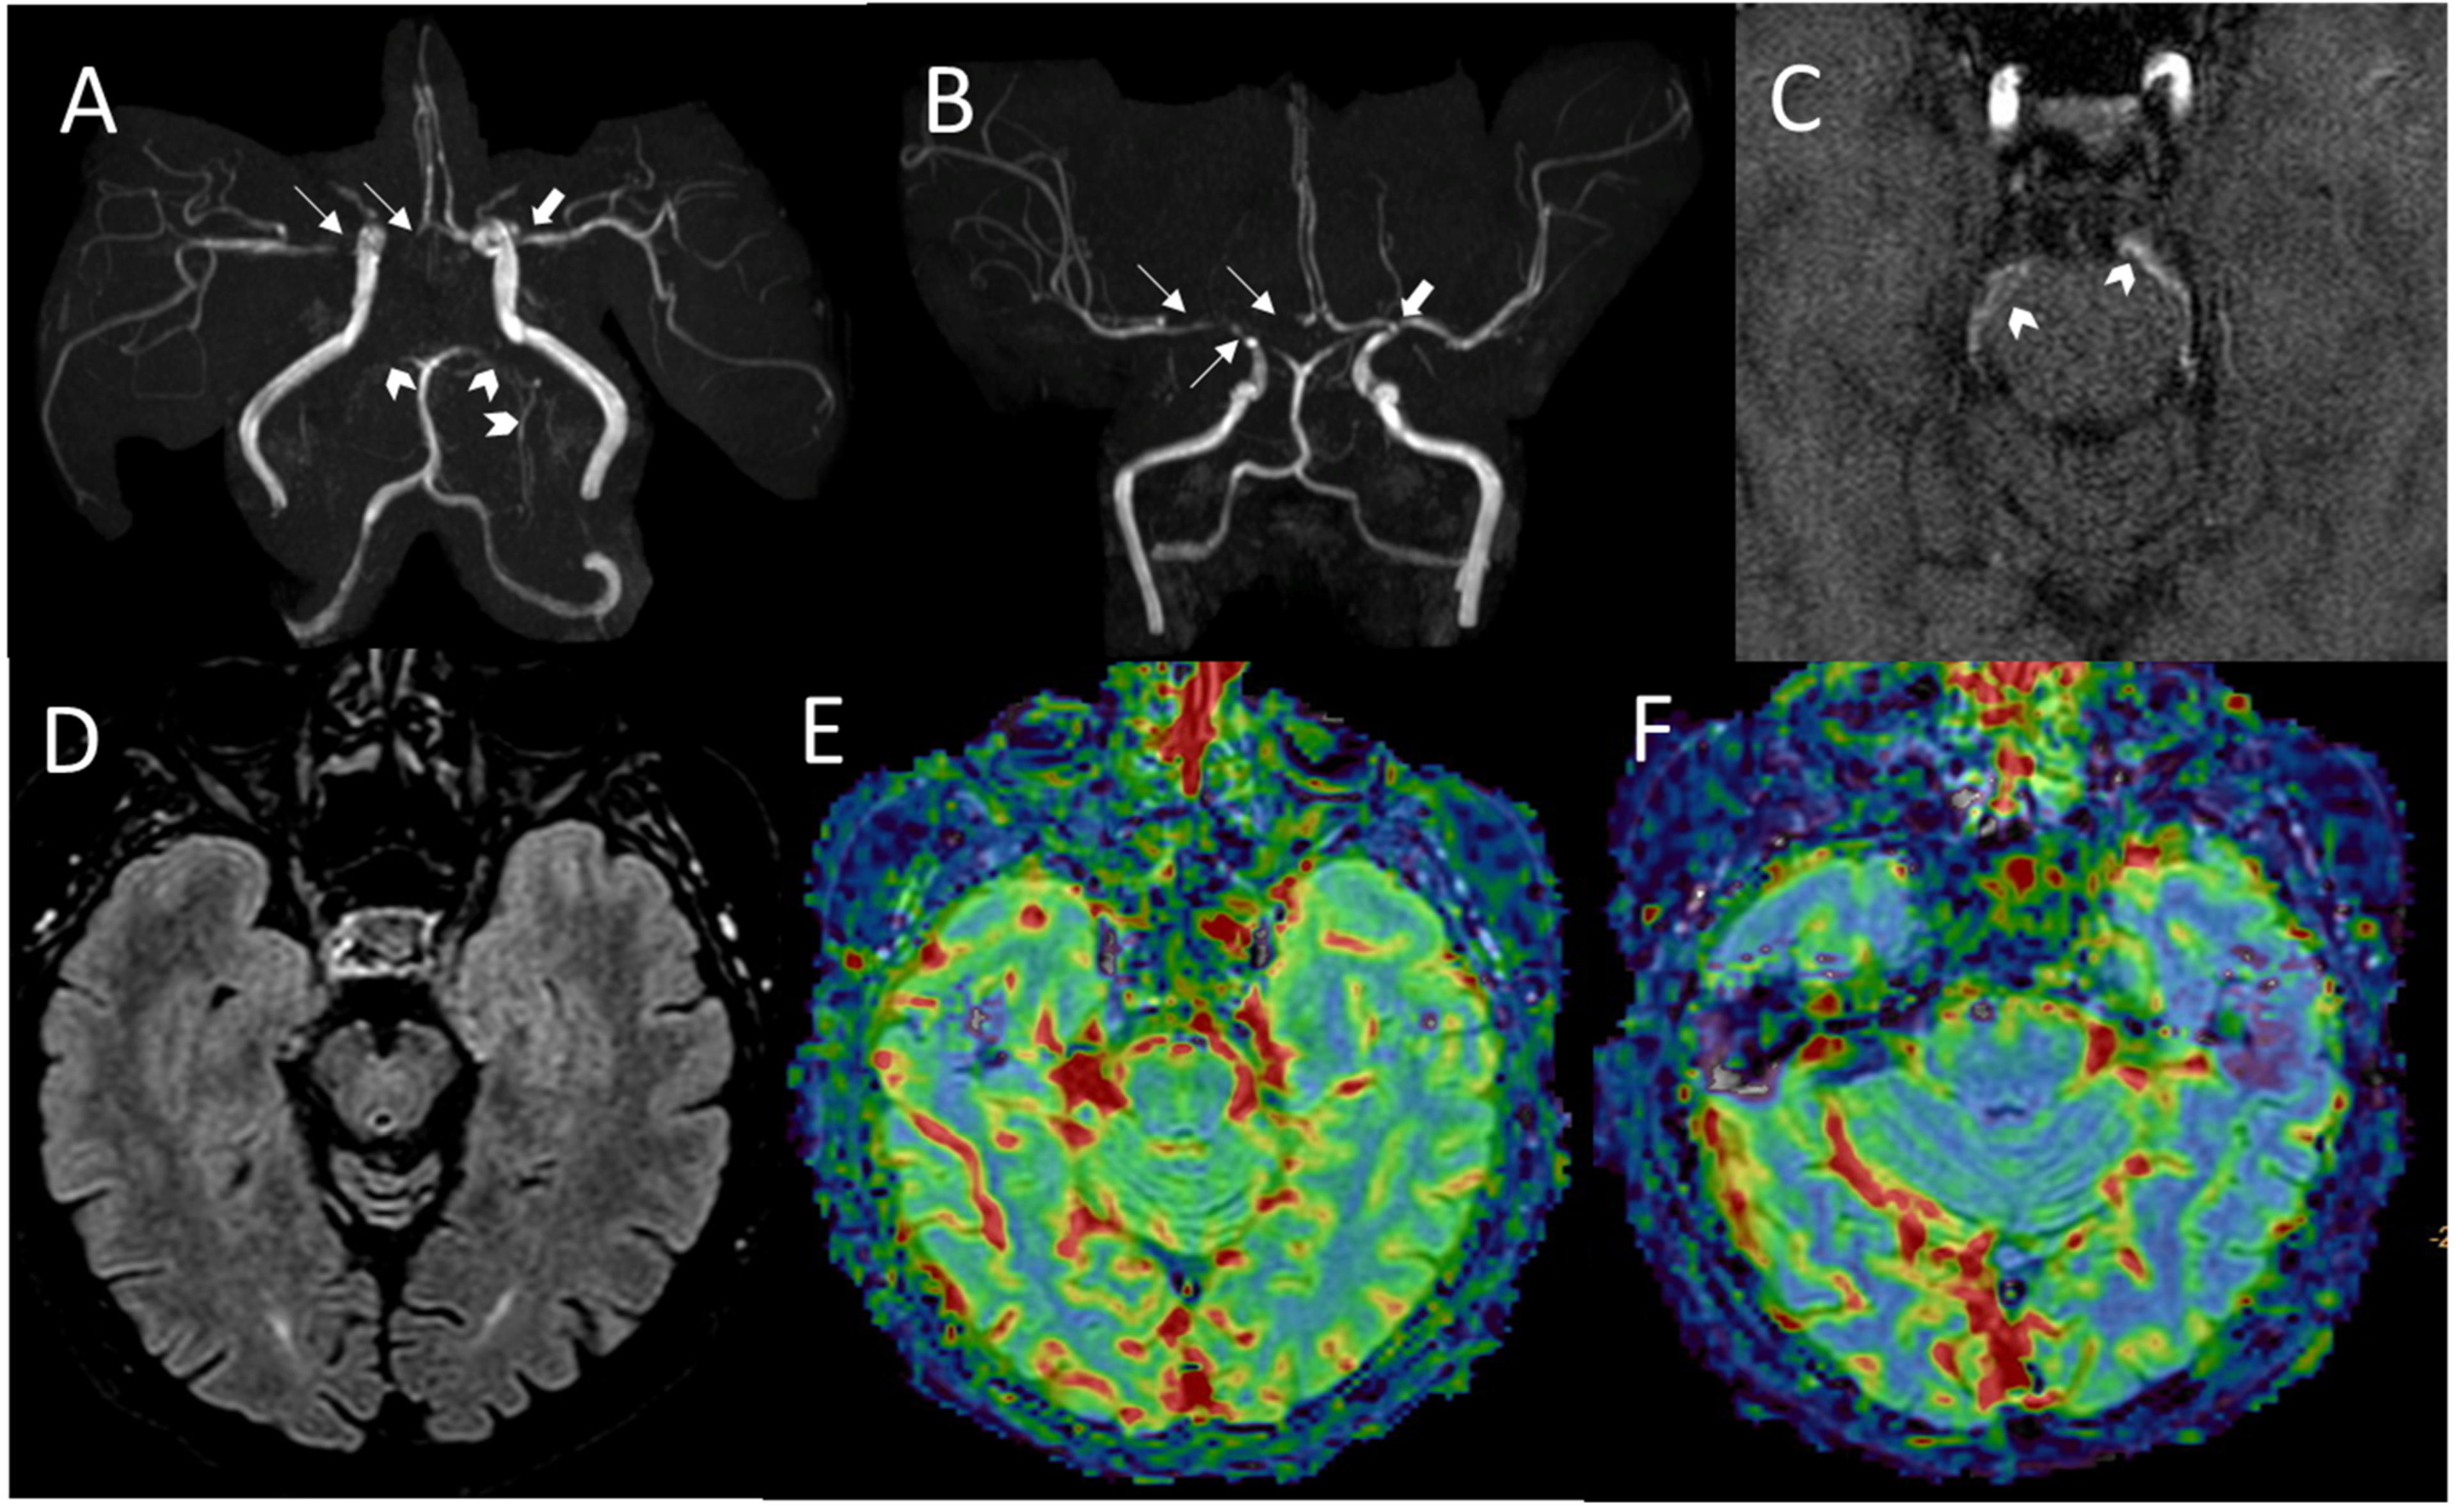

2.1. Family A

2.2. Family B

2.3. Family C